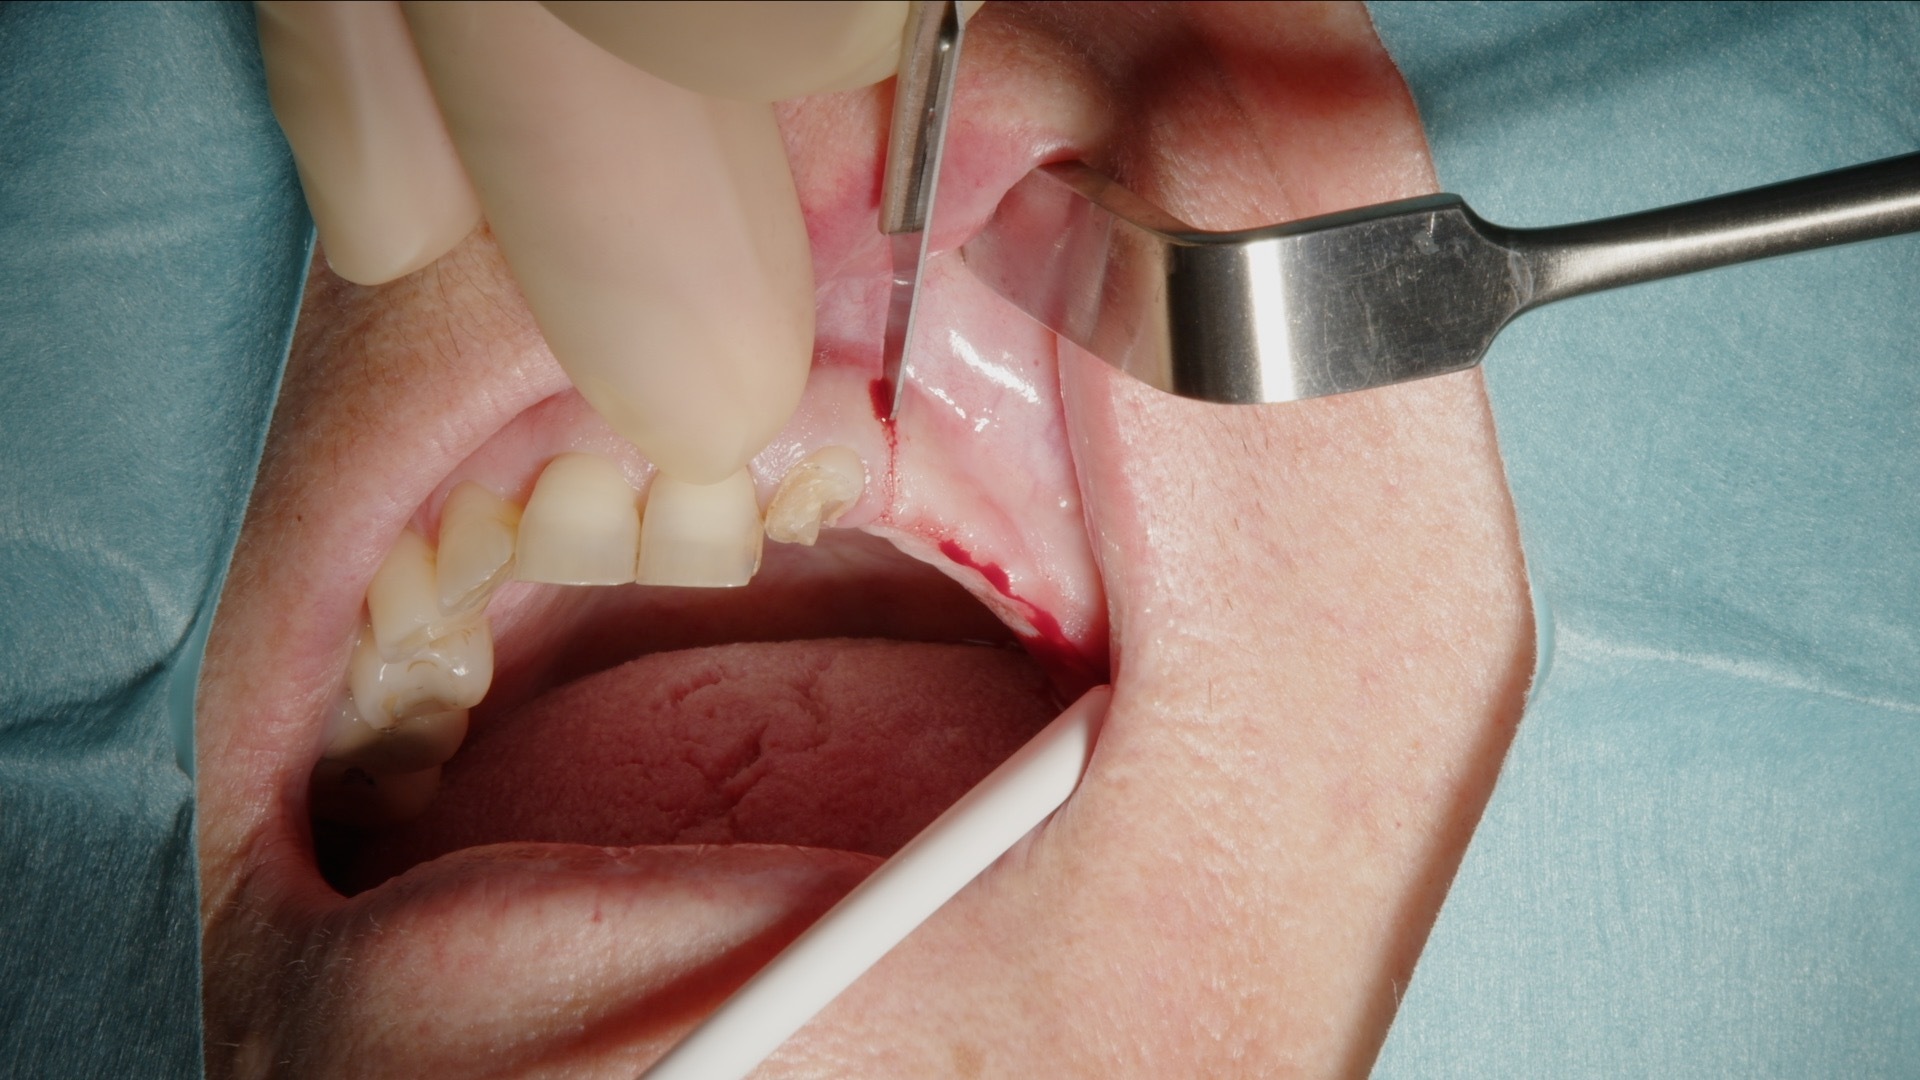

Det laterale vinduet prepareres konsekvent med Acteon Piezo Cube og diamantspiss. Den piezoelektriske teknologien muliggjør selektiv benbearbeiding med høy presisjon og minimal risiko for skade på bløtvev og sinusmembran. Instrumentet er ergonomisk, lett å manøvrere og gir god taktil kontroll, noe som bidrar til en effektiv og trygg prosedyre.

1. Incisjon og lappepreparering før etablering av lateralt vindu.

2. Preparering av lateralt vindu med Acteon Piezo Cube og diamantspiss.